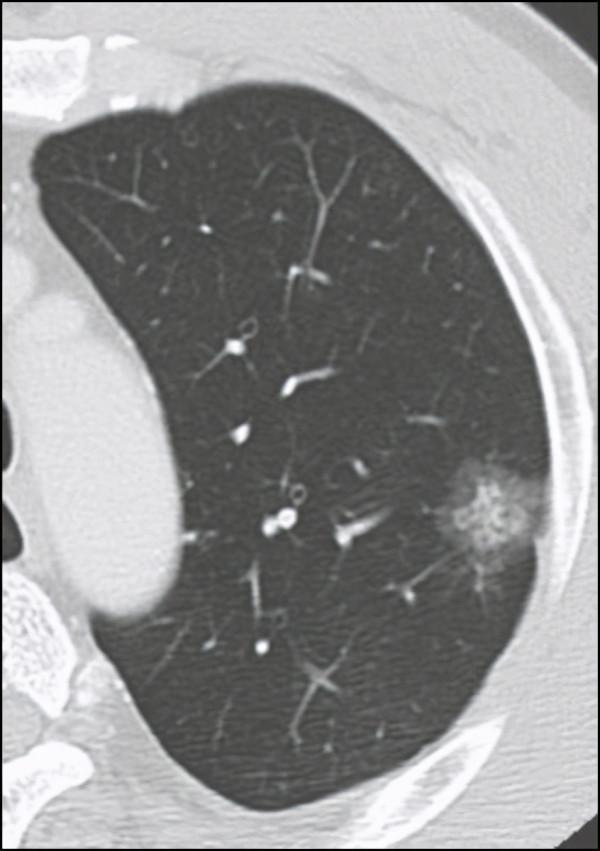

微波消融有點像微波爐的原理,使東西內部加熱升溫。微波消融是在CT引導下將一根微波針穿刺至腫瘤中心區域,由它釋放的微波磁場可以使周圍的分子高速旋轉運動並摩擦升溫,當溫度升高到60℃以上時,腫瘤細胞的蛋白質變性,細胞凝固、壞死,從而達到“燒死”腫瘤的目的,壞死的細胞逐漸被體內巨噬細胞所清除,其周圍的正常組織受較少損傷或不受損傷。

微波消融主要適用於原位肺腺癌或微浸潤肺腺癌患者、肺結節胸腔鏡術後發現新的高危肺結節,雙肺多發高危結節,全身情況無法耐受手術的早期肺癌患者、肺癌瘤體生長位置較差無法手術的患者。一般來說,3釐米以下的肺結節可以同時進行穿刺活檢和微波消融。